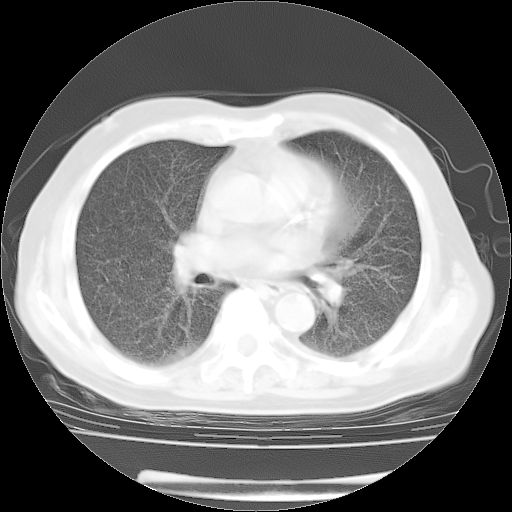

轻微咳嗽,无痰,(体温正常时)R20次/分,P75次/分,双肺底、腋下可闻及少量捻发音。下肢轻度浮肿。

ECG:右心室增大

心脏超声检查:无右心室增大。